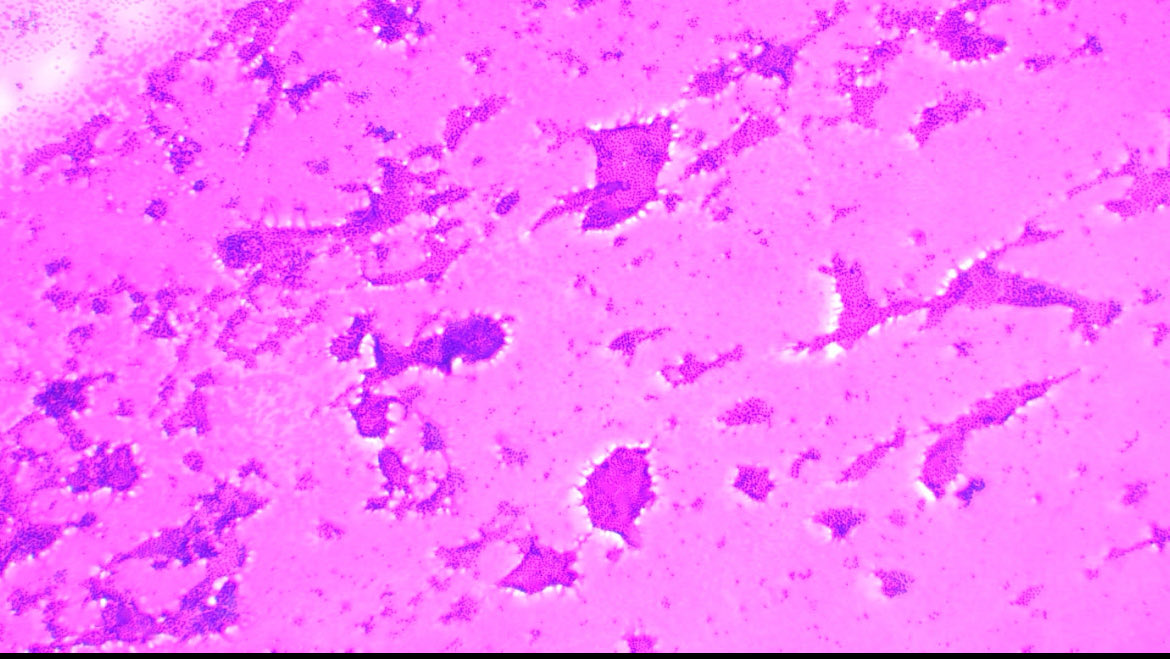

Who said benign lesions do not have hypercellular smears?🤔🤔 Here we have a hyperplastic nodule. The Giemsa stain shows abundant colloid. ⚖️ #cyto #cytology #path #thyroid